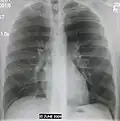

Normal AP CXR

Normal lateral CXR -